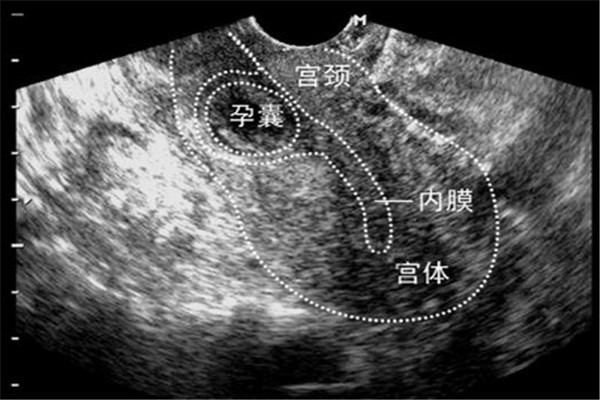

子宫内膜的品质:子宫内膜是胚胎着床的地方,子宫内膜如果厚度适当,血流丰富且细胞分裂良好,相当于肥沃疏松的土壤,会增加胚胎着床率,反之,若子宫内膜太薄,血流量不足,荷尔蒙分泌缺乏,这种内膜就相当于盐碱地,胚胎就不易着床。另外在植入胚胎的时候,子宫会有收缩的动作,有时候胚胎甚至会被推到输卵管,造成子宫外孕,所以胚胎植入后要有充分的卧床休息,补充足够的黄体素,以增加着床率减少外孕的比率